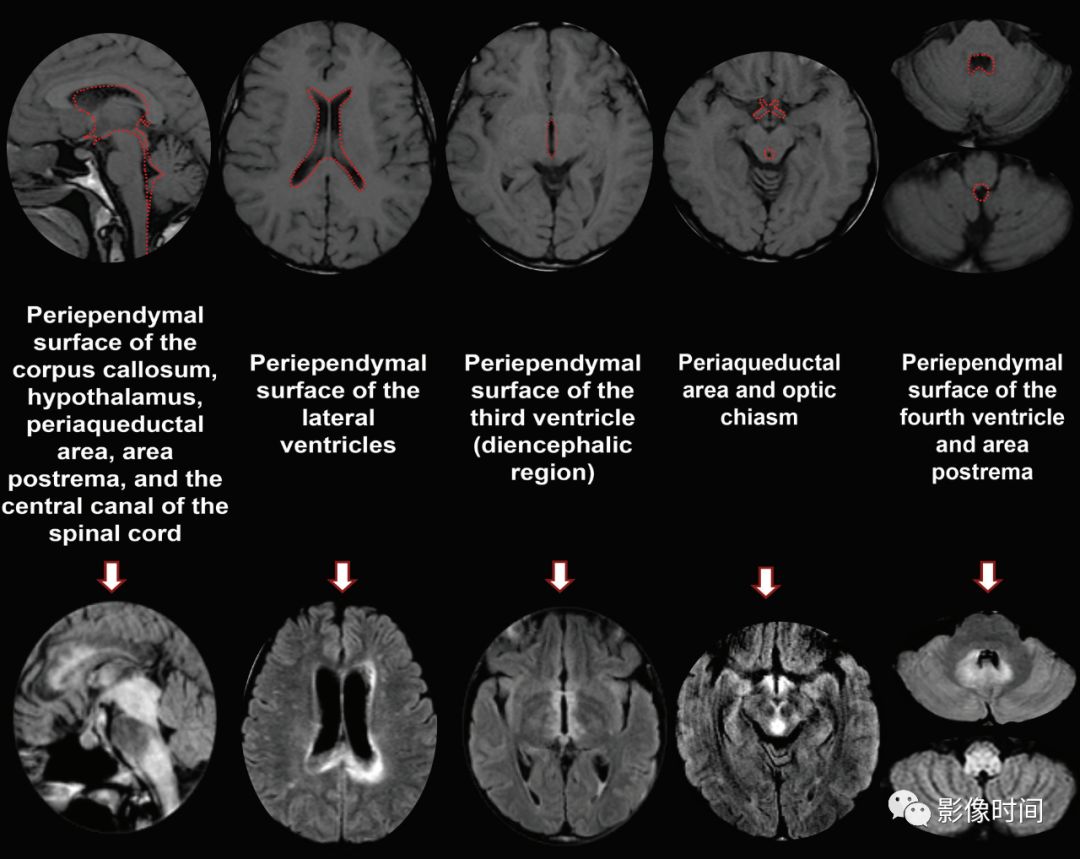

神经脊髓炎谱系疾病(neuromyelitis optica spectrum disorder,NMOSD):是一种由水通道蛋白-4(AQP-4)自身抗体介导的炎性脱髓鞘疾病,青年或中年女性较多见,临床常为双侧视神经炎和脊髓炎导致失明和截瘫,也可累及大脑。

MRI:

脊髓:病灶 T2WI 呈高信号,T1WI 呈稍低信号,急性期出现斑片状或云雾状强化,轴位常位于脊髓中央,长度>3 个椎体长度。亮点征:轴位 T2WI 很高信号的多发斑点,信号高于脑脊液,特异性=97%。

病灶分布于脊髓中央,长度大于3个椎体,亮点征

视神经:双侧视神经广泛受累,病灶长度通常>1/2 视神经长度,优先损害后视通路,包括视神经颅内段、视交叉和视束,急性期 T2WI 视神经肿胀伴明显高信号,T1WI 视神经明显强化,后视通路为主。

后视路受累为主,明显强化

大脑:AQP4 通道是中枢神经系统最丰富的水通道,在室管膜周围、下丘脑和软脑膜下区以及脑干、极后区均有高表达。因此,高表达 AQP4 的特定区域成为 NMO 自身免疫靶点